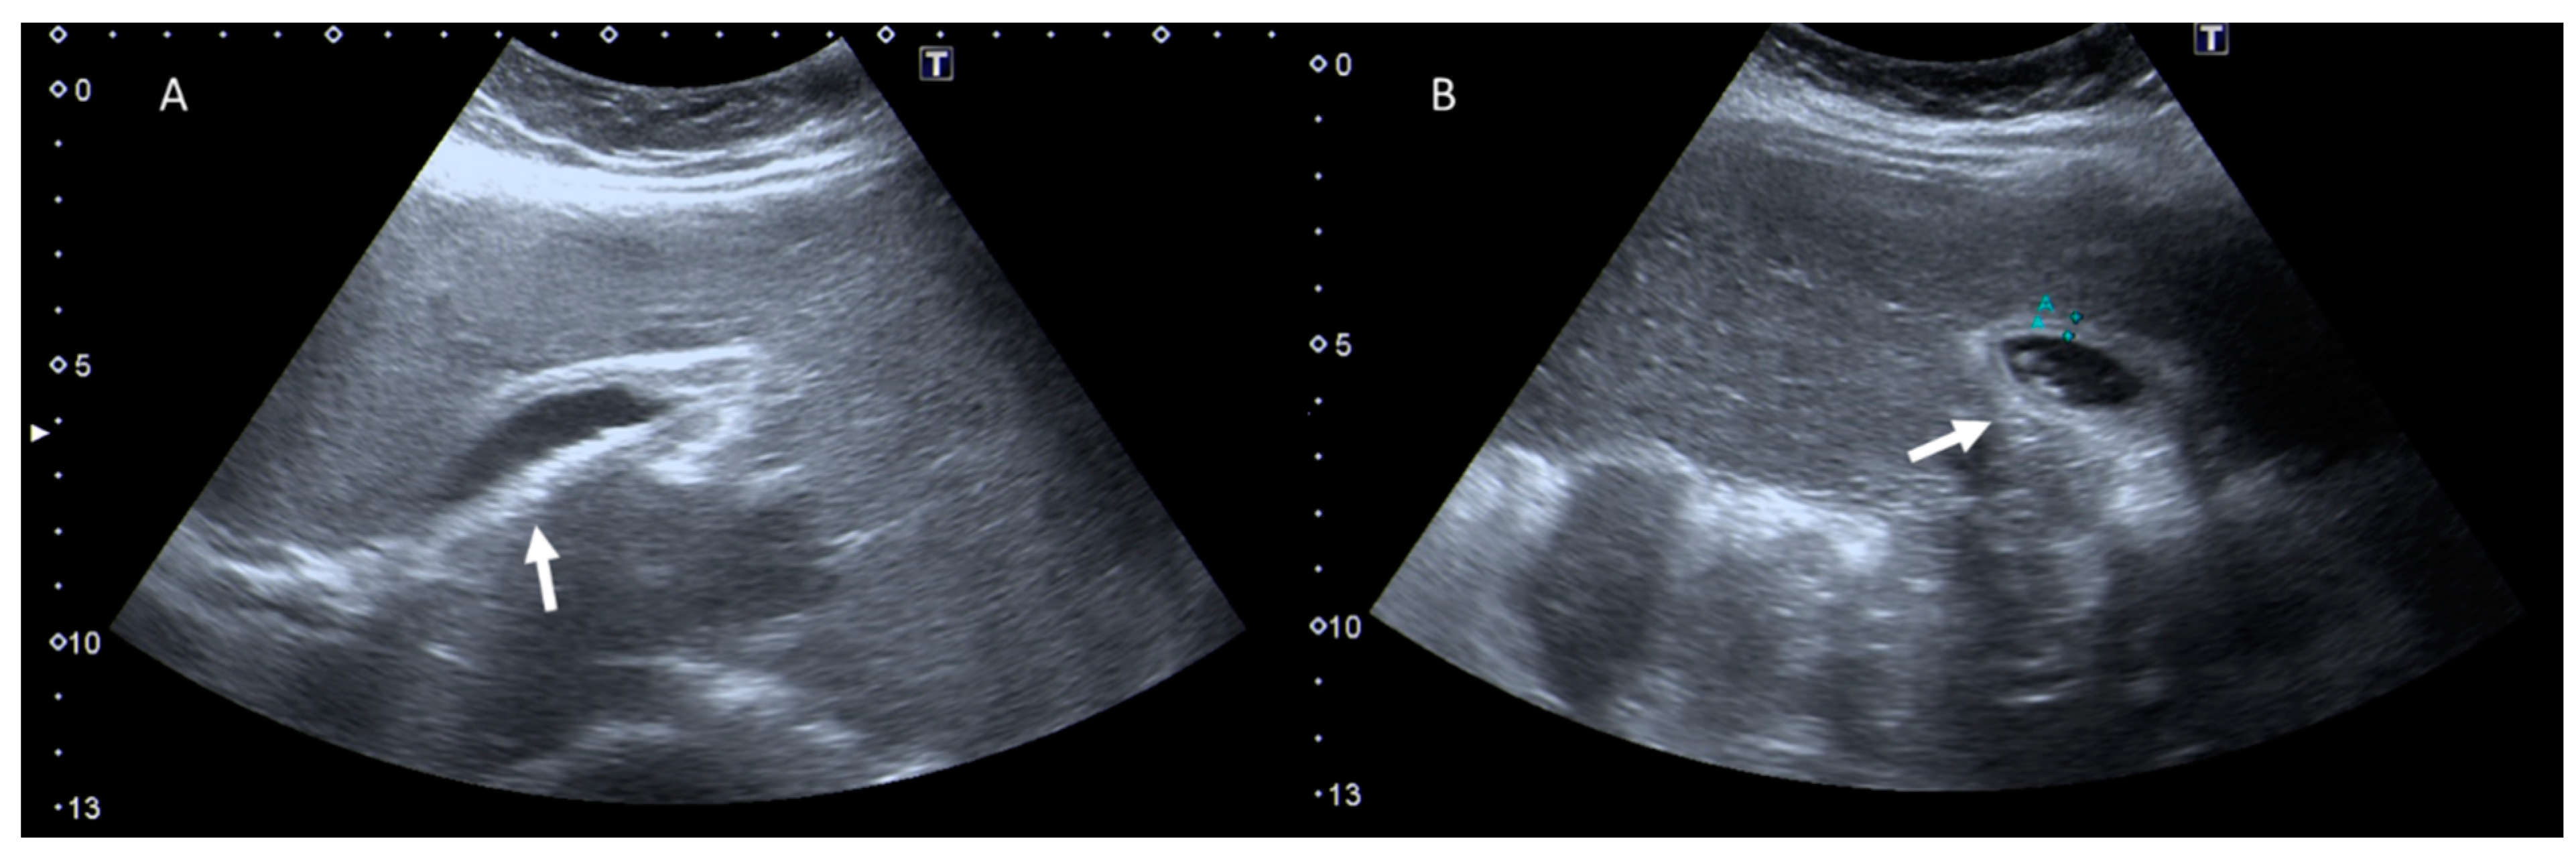

4. Clinical Setting: Abdominal Pain

5. Acute Appendicitis